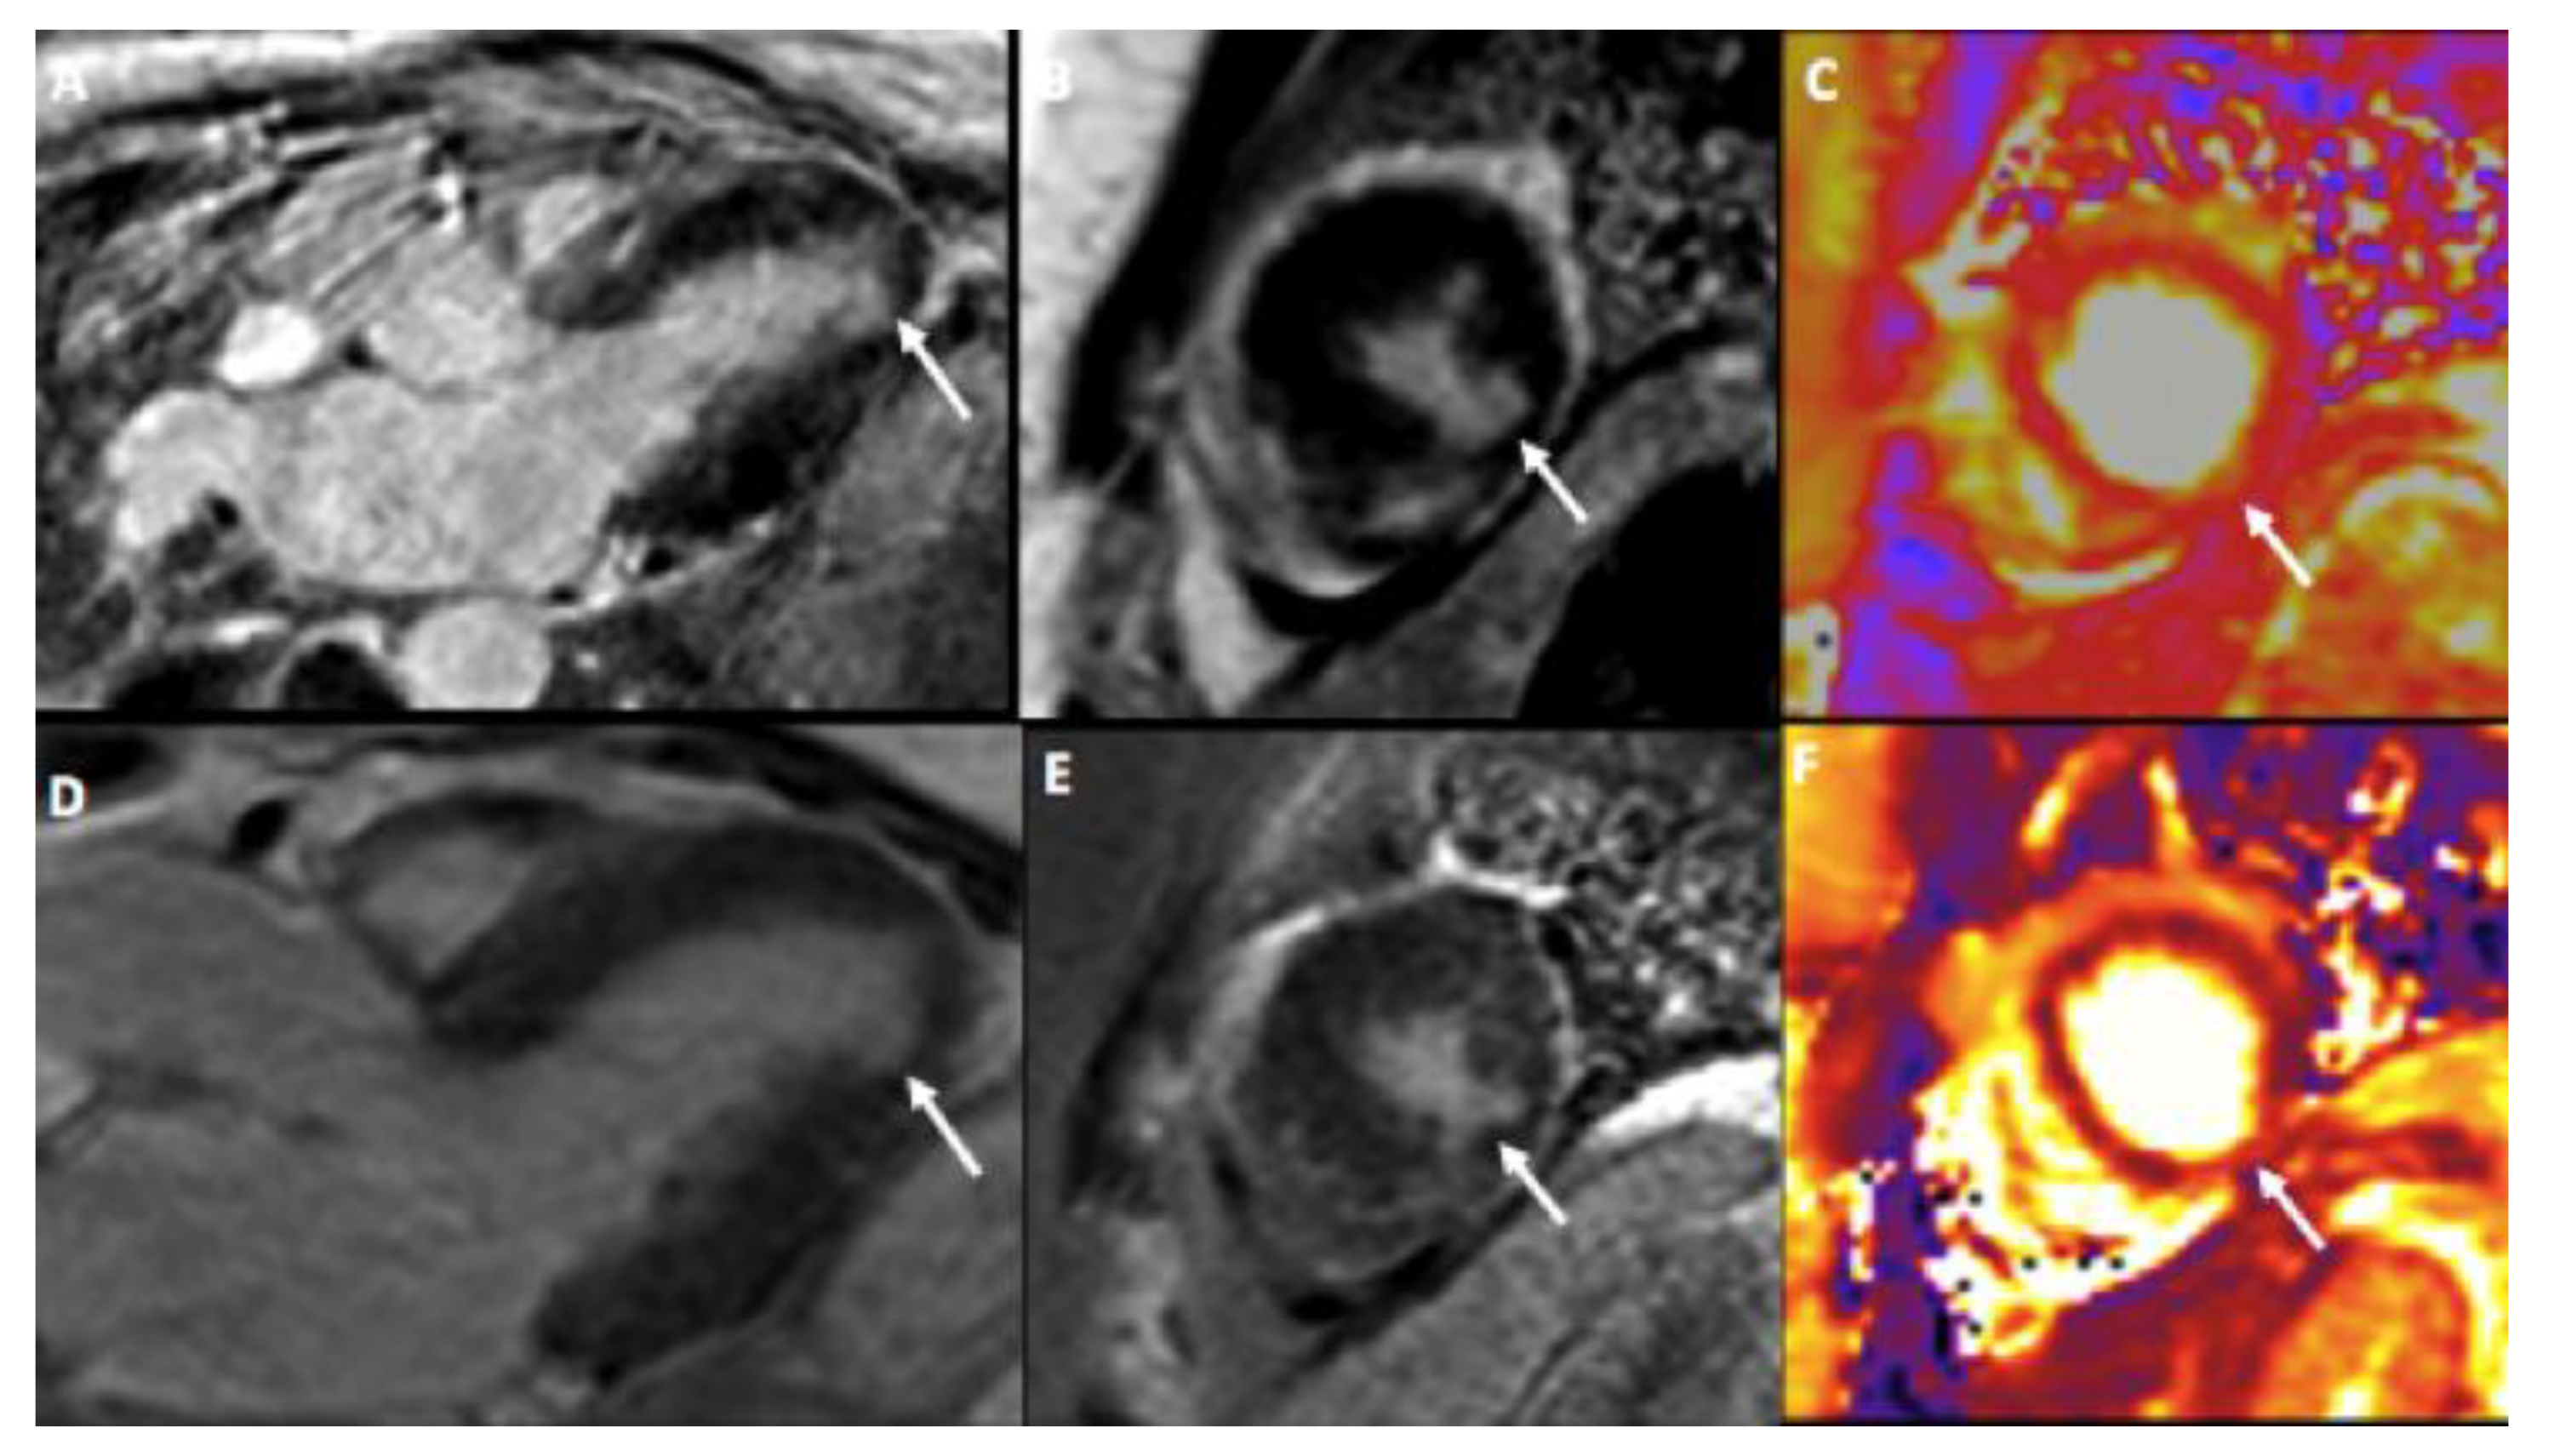

| Present case |

46, F | Allergic rhino-sinusitis and asthma | No | mRNA-1273 | 4 (2nd dose) | Enteritis, fever, fatigue, myalgia | Myocarditis, multiple strokes, immune thrombocytopenia | 8.4 | No | 2 | MP, P, IVIG, RPL, RTX, BEN |